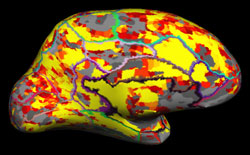

Projects in this area focus on increasing the speed of imaging acquisition, improving the spatial coverage of these imaging sequences, and developing innovative acquisition methods to enhance the spatial and temporal characteristics of anatomical, functional, vascular and metabolic brain signals. They are also concerned with improving the quantification of structural and functional brain images. Innovative software and algorithms are continuously being developed for use in brain segmentation, volume and cortical thickness determination, functional signal localization, as well as automated image processing and analysis pipelines.

Specifically, the lab combines neuroimaging measures such as functional magnetic resonance imaging (fMRI), diffusion tensor imaging (DTI), and other advanced neuroimaging as well as behavioral measures to identify prognostic factors that predict functional recovery, identify adaptive and maladaptive networks that contribute to functional recovery, and identify a critical time window for intervention in these patients. Our lab, in collaborations with Justin Williams’ Lab and TCNL, is developing Brain-Computer Interface (BCI) as well as cranial nerve noninvasive neuromodulation technologies as rehabilitation treatments for patients, which will lead to faster and more optimal levels of recovery.